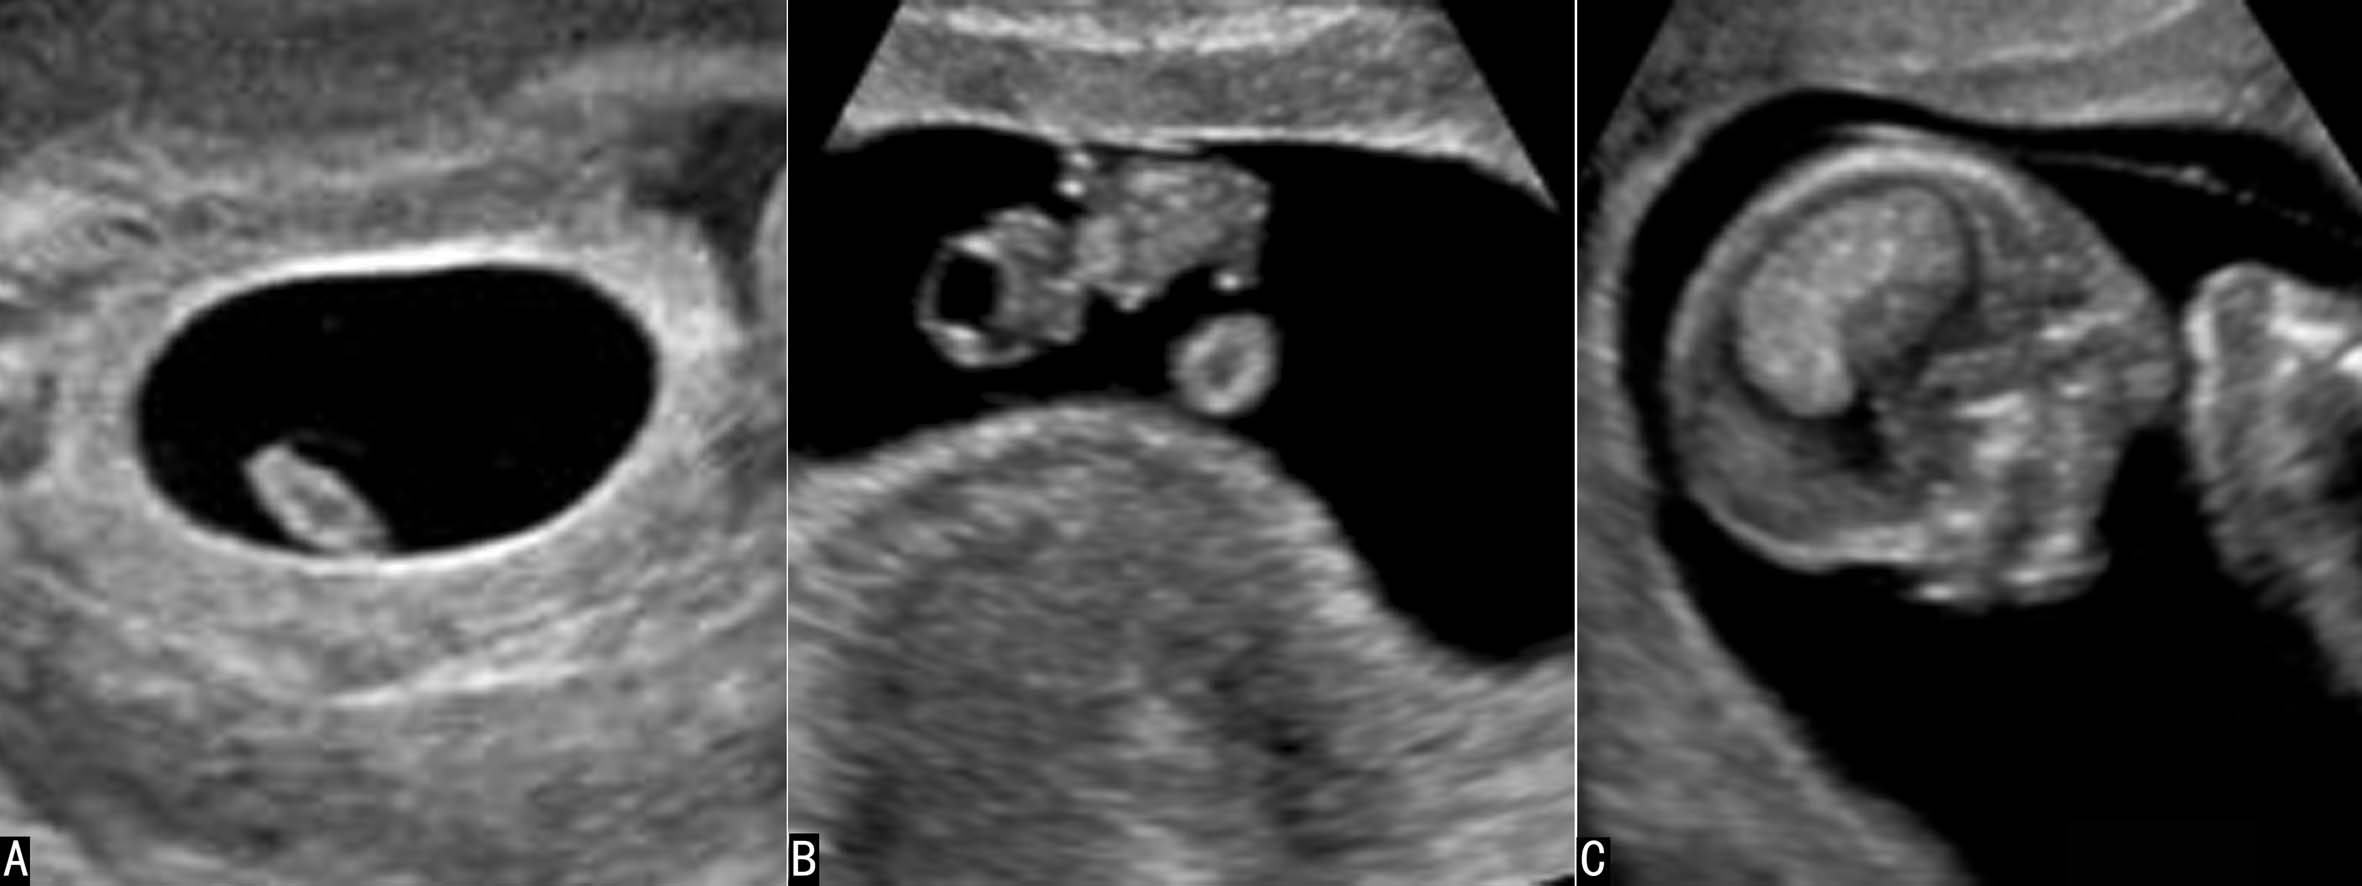

妊娠早期的羊水在声像图上显示为纯净的无回声区,胚胎或胎儿及脐带在羊水无回声区内显示得非常清楚(图1),直至中期妊娠的后期超声显像检查羊水内有时可以显示少量较低的点状回声(图2)。

图1早孕期羊水显示